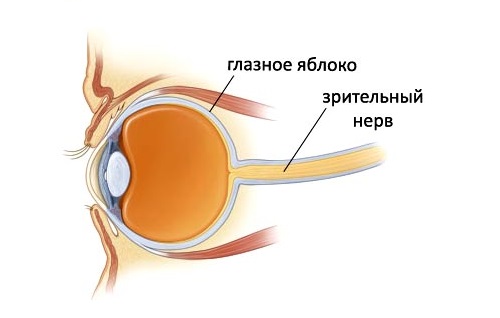

Атрофия зрительного нерва Лебера: Симптомы и лечение